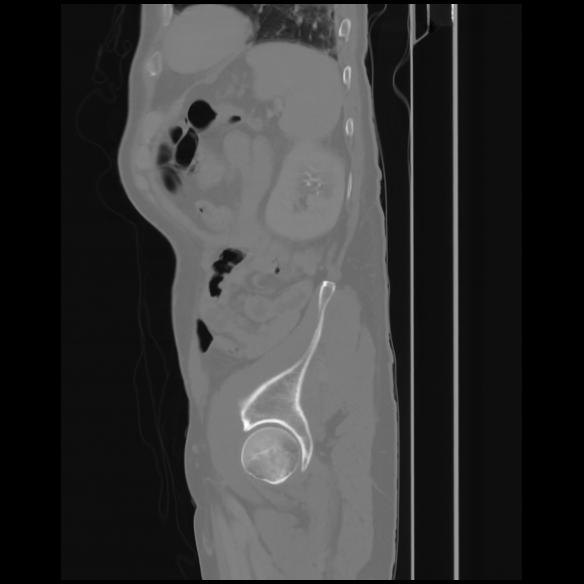

7 CUERPO,CE,Sagittal,3.000,CUERPO,Sagittal,